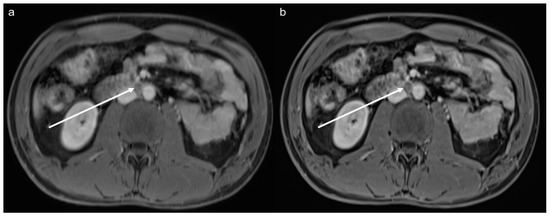

3.3. Qualitative Results of the Precontrast Images

3.4. Qualitative Results of the Postcontrast Images

3.5. Lesion Assessment